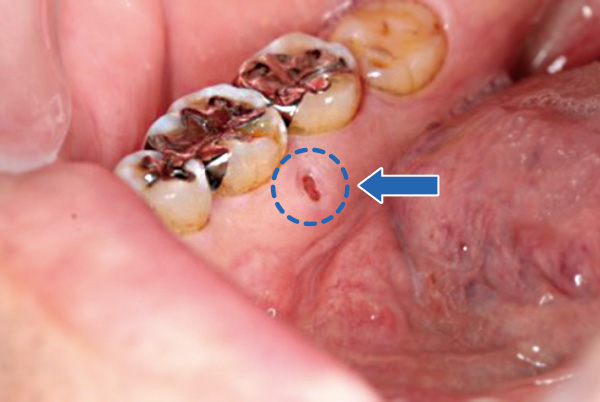

右下第一大臼歯舌側に骨露出を伴わない潰瘍を認めます。

歯科用CTでは同部の歯槽骨の一部喪失(矢印)が確認されます